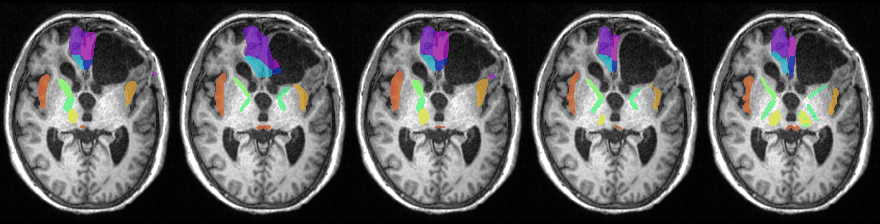

Segmentation Visualization

Left to Right: LT-Net, DeepAtlas, Brainstorm, Ours, and ground truth.